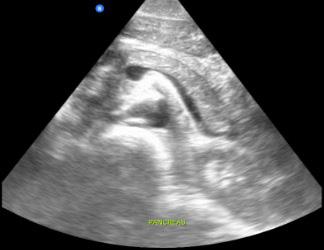

Dr. Artiga’s academic interests include ultrasound, education, and advocacy. Within SAEM RAMS, he has led initiatives such as the Ask-A-Chair educational podcast series, advocacy efforts related to unionization, social media campaigns to promote resident engagement, and the development of board review resources for emergency medicine certification. He has recently taught ultrasound to emergency medicine programs in Latin America.

It was an extremely humbling and eye-opening experience. I went to teach in my father’s country, El Salvador, where I had never visited before. I never truly understood the conditions he lived in beyond his words. All the issues that exist in the U.S. are magnified when you go to countries that don’t have similar resources. Medical decision making is limited by access to resources. It’s not about a lack of capability. I worked with incredibly brilliant doctors who just don’t have access to the same technology or infrastructure we have here. That’s why I believe in supporting ultrasound specifically in these settings. In capable hands, point-ofcare ultrasound can give a clinician life-saving information. Providing this tool and empowering physicians to use it can have a huge impact on individual patients and healthcare systems across the world.

For me, it’s been about chasing my passion and asking, “Who’s on this ride with me?” I’ve always been drawn to ultrasound. Through SAEM’s and the Academy for Emergency Ultrasound’s (AEUS’s) ultrasound didactics and activities, I’ve noticed similar faces showing up. These spaces allow for ideas to connect and develop in ways that don’t happen when you're working alone. You can’t have synergy in isolation. You need people who challenge and inspire you to promote growth. It’s individuals working together, learning from one another, and pushing ideas forward that produce progress.